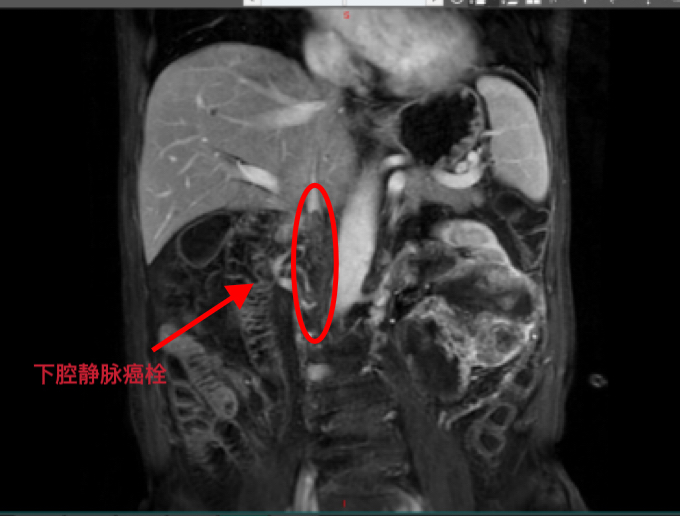

2021年,邬某因持续腰痛、血尿在外院就诊,CT检查显示左肾占位性病变,考虑肾癌;进一步检查发现癌栓已沿左肾静脉蔓延至下腔静脉,形成长约8厘米的充盈缺损影。穿刺病理确诊为肾细胞癌后,患者开始接受靶向药物治疗,病情一度稳定。

手术当日,团队采取“先右侧卧位取肾、再左侧卧位取栓”的分阶段策略。首先,在右侧卧位下精准游离,完整分离并切除左侧肾脏;随后将患者转为左侧卧位,以毫米级精度游离下腔静脉、右肾静脉及腰静脉,充分暴露下腔静脉癌栓段,并彻底阻断右肾静脉、下腔静脉近心端及远心端。切开下腔静脉后发现癌栓已侵犯血管壁,鉴于静脉侧支循环已形成,遂实施下腔静脉癌栓段节段切除术。术中,团队突破传统操作局限,创新应用“分段阻断血流”技术,既有效减少肾脏缺血损伤,又成功避免癌栓碎片脱落风险。